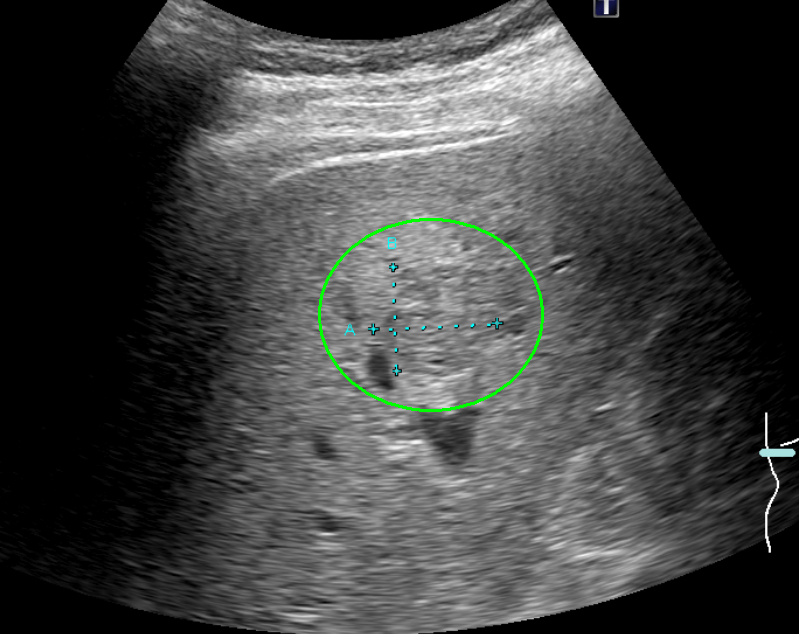

肝臓がんの検査としては、まず血液検査(肝機能検査、腫瘍マーカー検査)と超音波(エコー)検査を行います。必要により、CT検査もしくはMRI検査による画像検査も組み合わせて実施します。画像検査で良性/悪性の鑑別が難しい場合は、直接腫瘍組織を採取して調べる検査(針生検)を追加する場合もあります。

超音波検査画像